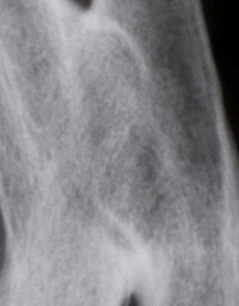

Иллюстрация 4. Структура костной ткани в области синостоза.